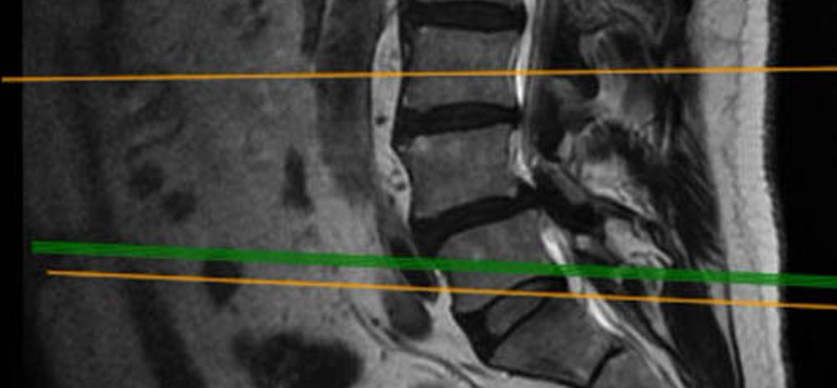

Caso clínico: endoscopia de columna multinivel L4L5 y L5S1

Los síntomas que presentaba el paciente eran dolores acentuados en las piernas, claudicación a la marcha y calambres y hormigueos en las piernas.

Durante la intervención quirúrgica, se abordarán los dos niveles mediante la técnica de endoscopia de columna.